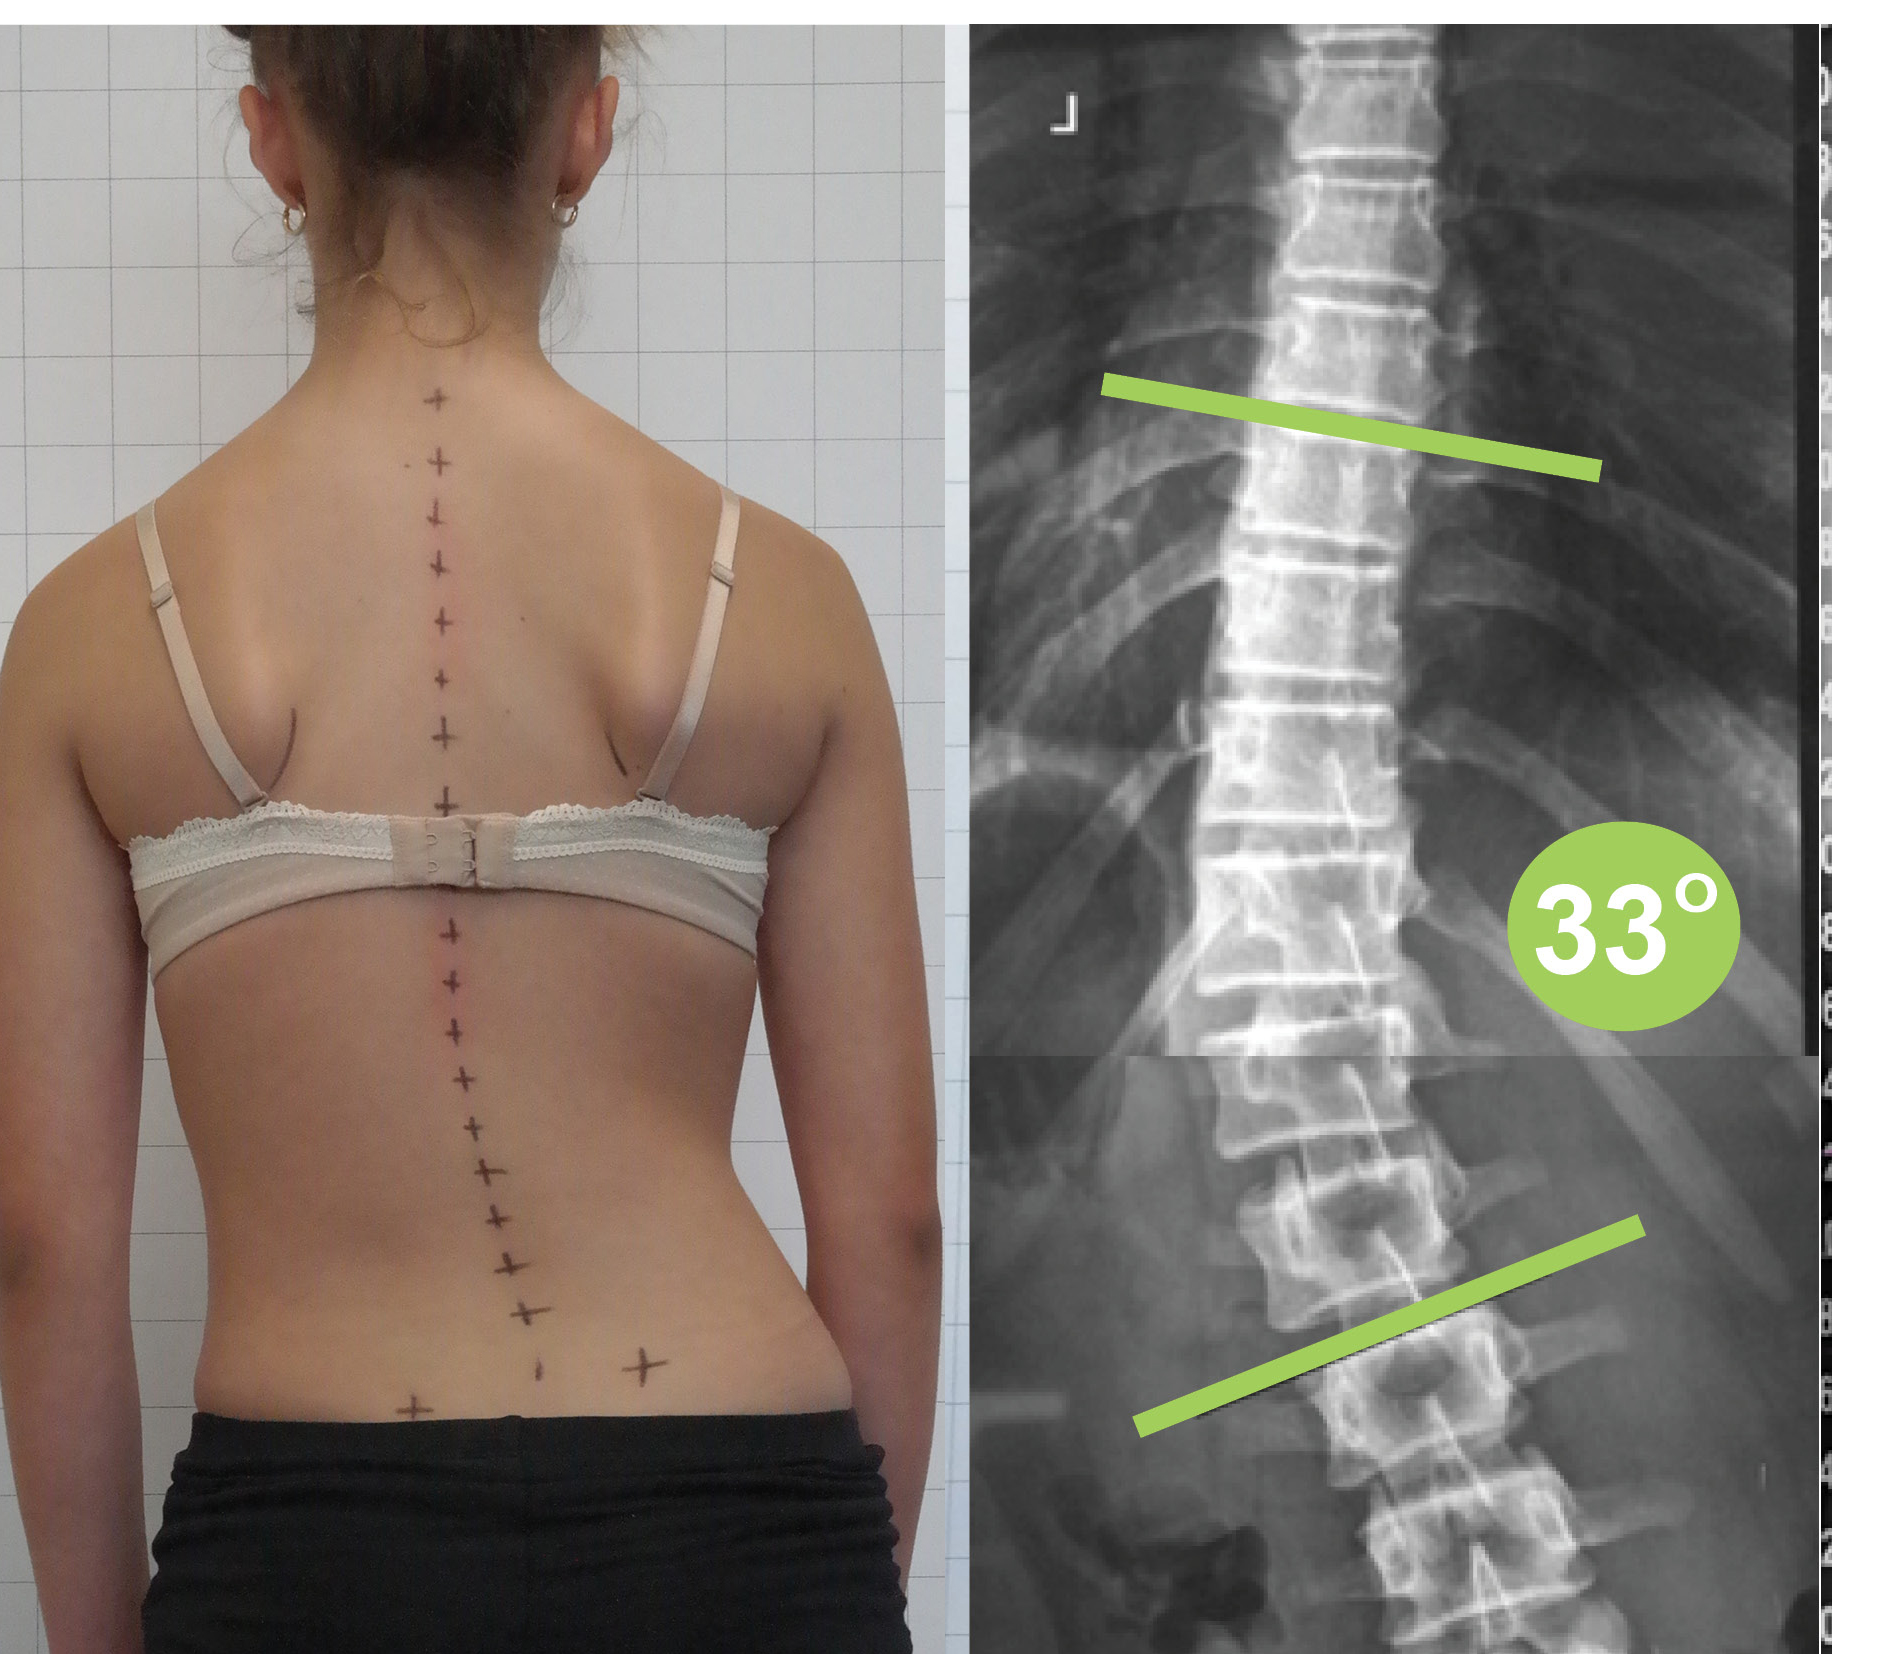

اعوجاج العمود الفقري القطني يعني وجود انحناء جانبي غير طبيعي في هذا الجزء من العمود الفقري، ويُقاس هذا الانحناء باستخدام الأشعة لتحديد درجته وشدته.

كيف يتم تشخيص اعوجاج العمود الفقري القطني؟

يعتمد التشخيص على مجموعة من الخطوات الأساسية، تشمل:

الفحص السريري ووضعية الجسم

تقييم مستوى الحوض والكتفين

الأشعة السينية لقياس زاوية الاعوجاج

هذه الخطوات تساعد الطبيب على اتخاذ القرار العلاجي الصحيح.